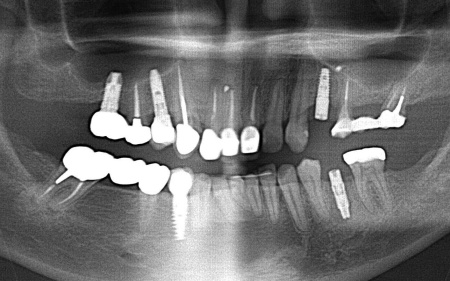

| 診断 | 拝見したところ、左上奥歯(第1小臼歯)は歯の上の部分である歯冠が折れ、歯根のみ残っている状態でした。 また、左下奥歯(第2小臼歯)には被せ物が装着されています。 レントゲン撮影をして痛みの原因を詳しく検査したところ、左上下奥歯の歯根が割れており、その影響で痛みが出ていると考えられました。 歯根が割れた歯は温存が難しく、このまま放置すると炎症が広がって周囲の歯に悪影響を及ぼすおそれがあるため、抜歯せざるを得ない場合があります。 以上のことから、温存が難しいと判明している左上奥歯は抜き、左下奥歯は被せ物を取り外して内部を確認したうえで、適切な処置を行うことが望ましいと診断しました。 |

| 行ったご提案・治療内容 | 診断結果をお伝えし、患者様の了承を得たうえで左下奥歯の被せ物を外したところ、レントゲン検査での診断どおり、歯根が割れていることが確認できました。 そのため、患者様には左上下奥歯とも温存が難しい旨を説明し、抜歯に同意いただきました。 患者様は、以前当院で人工歯根を顎の骨に埋入して歯を装着するインプラント治療を受けていたため、今回も左上下奥歯ともインプラント治療を希望されています。 メリット デメリット 改めてメリットとデメリットをしっかりお伝えしたところ、インプラント治療に対する不安はないとのことで、治療に同意いただきました。 まず、左上下奥歯を慎重に抜きます。 インプラント手術後は経過観察を行い、インプラントが顎の骨に結合したことを確認したら、インプラント上部に取り付ける人工歯を作製するために精密な型取りを実施します。 後日、完成した人工歯をインプラントに装着し、使用感や見た目に問題がないことを確認して、治療を終了しました。 |